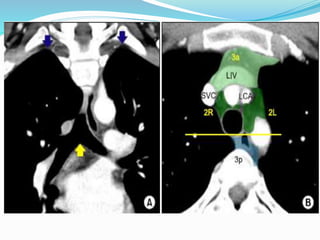

Station 1

 Low cervical, supraclavicular and sternal notch nodes

 Upper border : Lower margin of cricoid cartilage

 Lower border : Clavicle bilaterally and in midline upper

border of manubrium

Upper zone

Station 1  Lowcervical, supraclavicular and sternal notch nodes  Upper border : Lower margin of cricoid cartilage  Lower border : Clavicle bilaterally and in midline upper border of manubrium